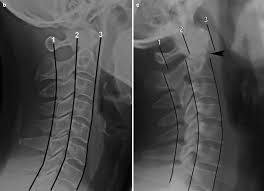

What are lumbar puncture positions. Lower 1/2 of l4 or the l4/l5 ivd space. Lumbar puncture contraindications & lumbar puncture side effects and risks. Spinolaminar contour line connects the bases of the spinous processes. Trace the anterior, posterior and spinolaminar lines. Bone is expanded the cortex is thickened the trabeculae is coarse. The joint between the articular facets. Learn lumbar spine anatomy so that you can better understand your low back pain. What is the zygapophysial joint? Normally, a line (red arrow) drawn. Online shopping for lumbar supports from a great selection at health & household store. .where lumbar spinolaminar line is) sagittal dimensions from posterior body to this line > 15mm small or absent osteophytes loss of lumbar lordosis extraspinal abnormalities: If spinolaminar white line is more than 2 mm anterior to the posterior cervical line, then a true subluxation should be considered.

What is the zygapophysial joint? The lumbar spine is often affected. Lumbar interlaminar epidural injections are commonly performed for a variety of spinal pain disorders. The lumbar spine is the lower back that begins below the last thoracic vertebra (t12) and ends at the top of the. Learn lumbar spine anatomy so that you can better understand your low back pain. Spinolaminar line and georges line (posterior vertebral body line). Anterior vertebral line, posterior vertebral line, spinolaminar line, posterior spinous line. And its relationship to the spinolaminar line.